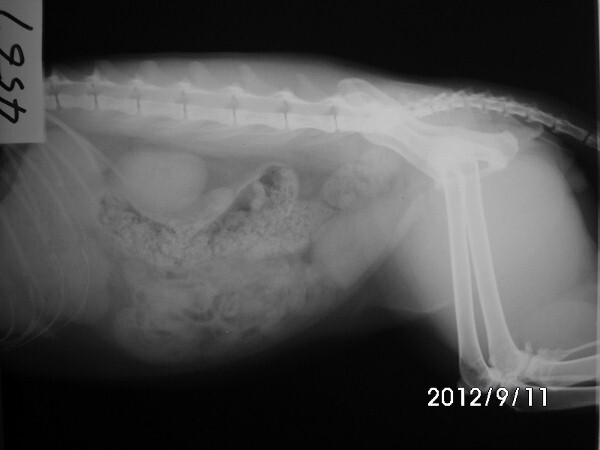

主題: 桂田街 眼睛感染 泌尿道有問題的橘公貓 申請者姓名: 劉雅雲 花色: 申請日期: 2012-09-18 22:30:52 申請者部落格: 申請者臉書網址: 所在縣市/合作醫院: 高雄市/樂生動物醫院 治療費用: 5700元 需求人數: 13人 已結案 (2013-06-27 13:38:03) 報名人員: 阮驛琇(已付款)、姚怡君(已付款)、瑄瑄(已付款)、Leah(已付款)、Pei Jing Gao(已付款)、李孟儒(已付款)、王踢娜(已付款)、Rong Chen(已付款)、Rong Chen、Ginny Cat(已付款)、dowdot(已付款)、KiKi(已付款)、Wen Lin(已付款)、Wen Lin(已付款)、 候補人員: 動物病情說明: 桂田街已經結過紮的橘白公貓, 三年前結紮後跟他的夥伴們在這邊定點餵養, 日前發現眼睛感染越來越嚴重, 又一直有蹲著尿尿的動作, 好像尿不太出來, 很常看到他在蹲, 懷疑有尿道結石或感染的問題. 醫生幫他驗血看有無感染現象, 還有X光照看看有沒有結石, 住院打點滴促進排尿並觀察. 檢查時發現有口腔問題並幫他拔牙與洗牙, 還好沒有尿道結石的問題, 目前治療後眼睛和排尿的狀況已改善, 目前放回原地, 持續餵藥一週和滴眼藥水.

明細如下:

9/11 - 9/17 注院治療 7天 x 300 = 2100

血檢費用 1500

X光照 400 * 2 =800

麻醉洗牙及拔犬齒費用共 1150

眼藥水 150

Total: 5700